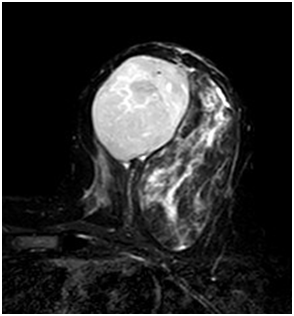

A 47year-old woman with history of a long standing palpable mass on the left breast, which was biopsied on 2006 resulting in hamartoma. She had first degree familiar history of breast cancer with her mother diagnosed younger than 50 \years of age and who later on died of that cause. The patient presented to our office, in June 2016 for progressive growth of her breast tumour. At examination her breasts were fibrous, with a palpable firm and mobile breast mass, not fixed to skin, of 8x6x5cm on the left LIQ, and another large, soft and well defined mass in left LOQ and UOQ of 10x10x5cm, There were no palpable masses in the axilla. On mammography there was a radiolucid well defined breast mass in the left LOQ and UOQ, which was stable in size and shape regarding prior mammogram of twoyears. A new dense, oval and partially defined breast mass was evident in the LIQ (Figure 1). The latter on breast ultrasound corresponded with a hypoechoic and heterogenous nodule with partially defined margins, which measured approximately 7cm. The first lesion was heterogenous and hyperechoic, measured more than 8cm, and was the previously biopsied nodule (Figure 2). She later on underwent a breast MRI that showed a round mass in the LIQ, which was hyperintense in T2, hypointense in T1, had a homogenous enhancement with a plateau curve. In the LOQ there was a well-defined mass, which was heterogenous with fibrous and fatty tissue, and did not enhance with gadolinium (Figure 3). A core biopsy of the two masses was then performed, demonstrating a biphasic fibro-epithelial lesion compatible with a PT at the LIQ, and fibrocystic changes and intraductal hyperplasia without atypia at the LOQ. On August 2016, the patient underwent a partial mastectomy, without incidents, and was sent home on the subsequent day (Figure 4). The definitive biopsy demonstrated that the tumour at the LIQ corresponded to a malignant PT (Figures 5) (Figure 6), and that the LOQ mass was a large breast hamartoma (Figures 7 & Figure 8). Posteriorly, she received 25 radiotherapy fractions, without major adverse effects. She was recently controlled with breast ultrasound and MRI that showed no residual breast lesions.

Figure 3 Preoperative breast MRI (T2 weighted image, T1 weighted image, STIR and gadolinium enhanced high resolution T1WI with fat saturation).